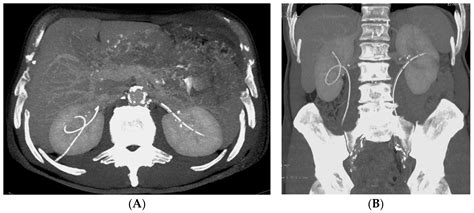

The stent is typically made of medical-grade plastic or silicone, designed to be biocompatible, meaning it can safely remain inside the body for a specific period. It features small curls at both ends—one sitting in the kidney and the other in the bladder—which act as anchors to keep the device from moving out of place. This design is why they are often called "double-J" or "pig-tail" stents.

4. Stent Placement: The stent is threaded over the guidewire and moved into the correct position. Once verified using X-ray imaging (fluoroscopy), the guidewire is removed, leaving the stent in place.